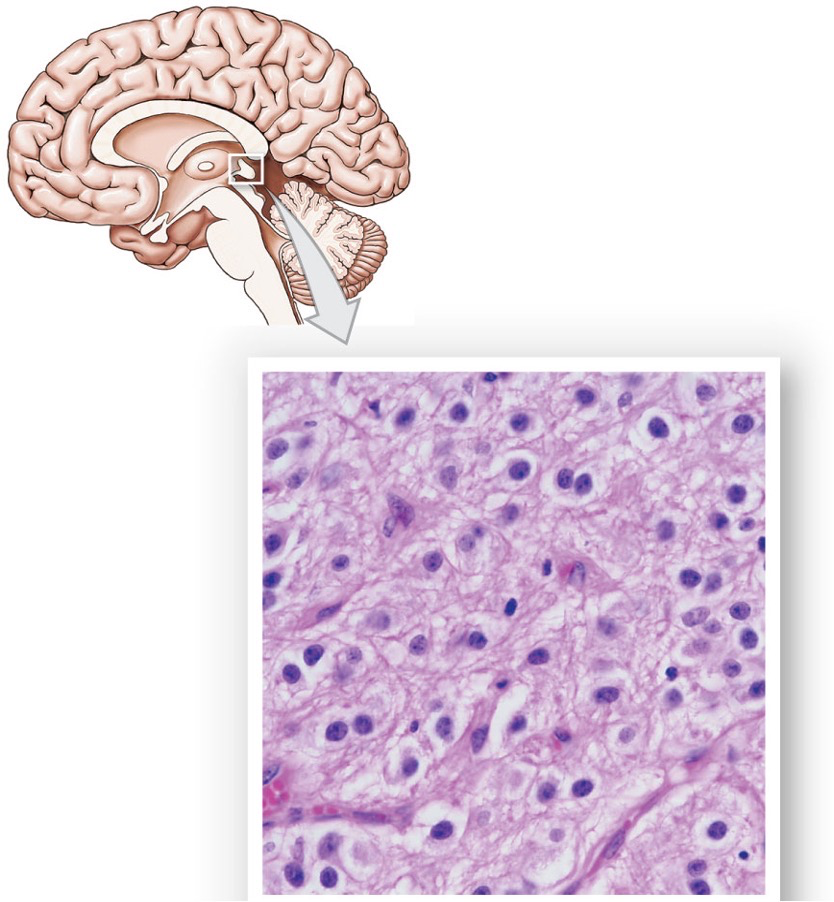

What does the pineal gland contain?

Neurons

Pinealocytes

What does the pineal gland look like?